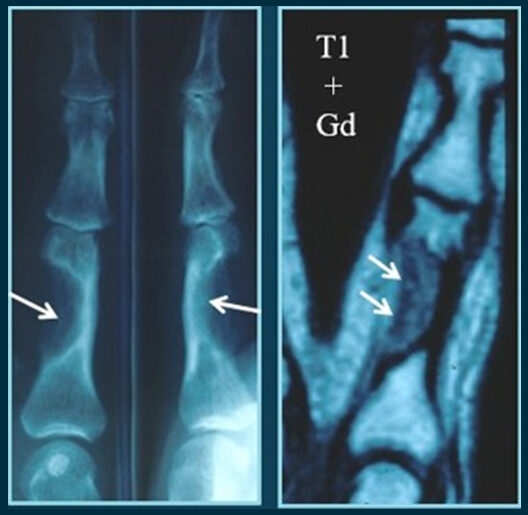

Displasia fibrosa en la Falange Proximal de un Dedo Meñique

Carlos IRISARRI | Sergio POMBO EXPÓSITO